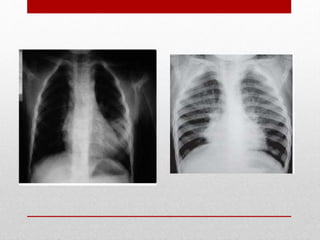

• Radiografía de tórax

Radiografía de tórax

• Radiología